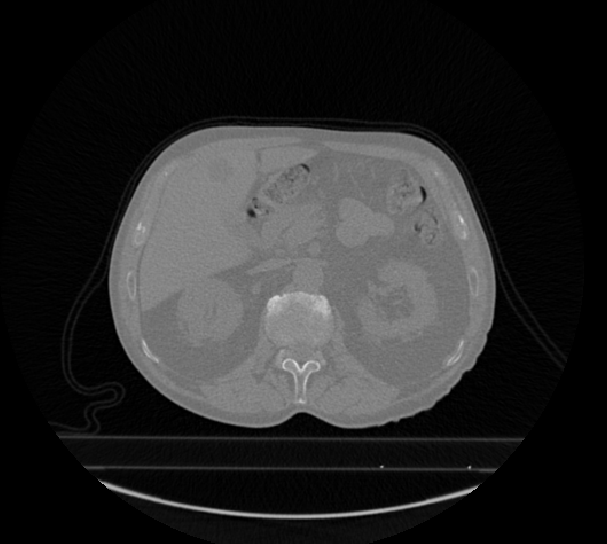

2.1 直方图特征(Histogram Features) 本类特征主要通过统计病灶部位的灰度强度信息(或亮度信息),然后考察病灶部位灰度强度信息的整体分布情况。图2分别描述的是带病灶的乳腺MR图像,其中病灶部位用红色的多边形线段标识出来。假设对图2.a和2.b的病灶部位求直方图特征,将有如下情况:

a b 图2. 带病灶的乳腺MR图像; 红色多边形表示病灶区域

Mean:均值,描述的是图像整亮度信息,若亮度越大,则Mean越大。假设图2.a病灶部位的亮度信息小于图2.b,则可以表达为Mean& #40;2.a& #41;< Mean& #40;2.b& #41;; Variance:方差,描述的是图像亮度信息的变化,若变化程度越大,则Variance越大。假设图2.a病灶部位的亮度变化小于图2.b,则可以表达为Variance& #40;2.a& #41;< Variance& #40;2.b& #41;; Unifomity:均匀性,描述图像亮度信息的均匀程度,若均匀程度越大,则Unifomity越大。假设图2.a病灶部位的均匀程度大于图2.b,则可以表达为Unifomity& #40;2.a& #41;> Unifomity & #40;2.b& #41;; Skewness:偏度,描述图像亮度信息分布的偏向性,若图像明亮区域信息比灰暗区域信息分布多,则Skewness值为正。如图2可知,Skewness& #40;2.a& #41;为负,Skewness& #40;2.b& #41;为正; Kurtosis:峰度,描述图像亮度信息的集中程度,若集中程度越大,则Kurtosis值越大;假设图2.a病灶部位亮度信息集中程度小于图2.b,则可以表达为Kurtosis& #40;2.a& #41;<Kurtosis & #40;2.b& #41;; Energy: 能量,描述图像亮度信息变化的剧烈程度,若变化越小,则Energy越大;如图2可知,Energy& #40;2.a& #41;>Energy& #40;2.b& #41;; Entropy:熵,描述图像亮度信息分布的复杂程度,若分布越复杂,则Entropy越大;假设图2.a病灶部位亮度信息复杂程度小于图2.b,则可以表达为Entropy & #40;2.a& #41;<Entropy & #40;2.b& #41;。